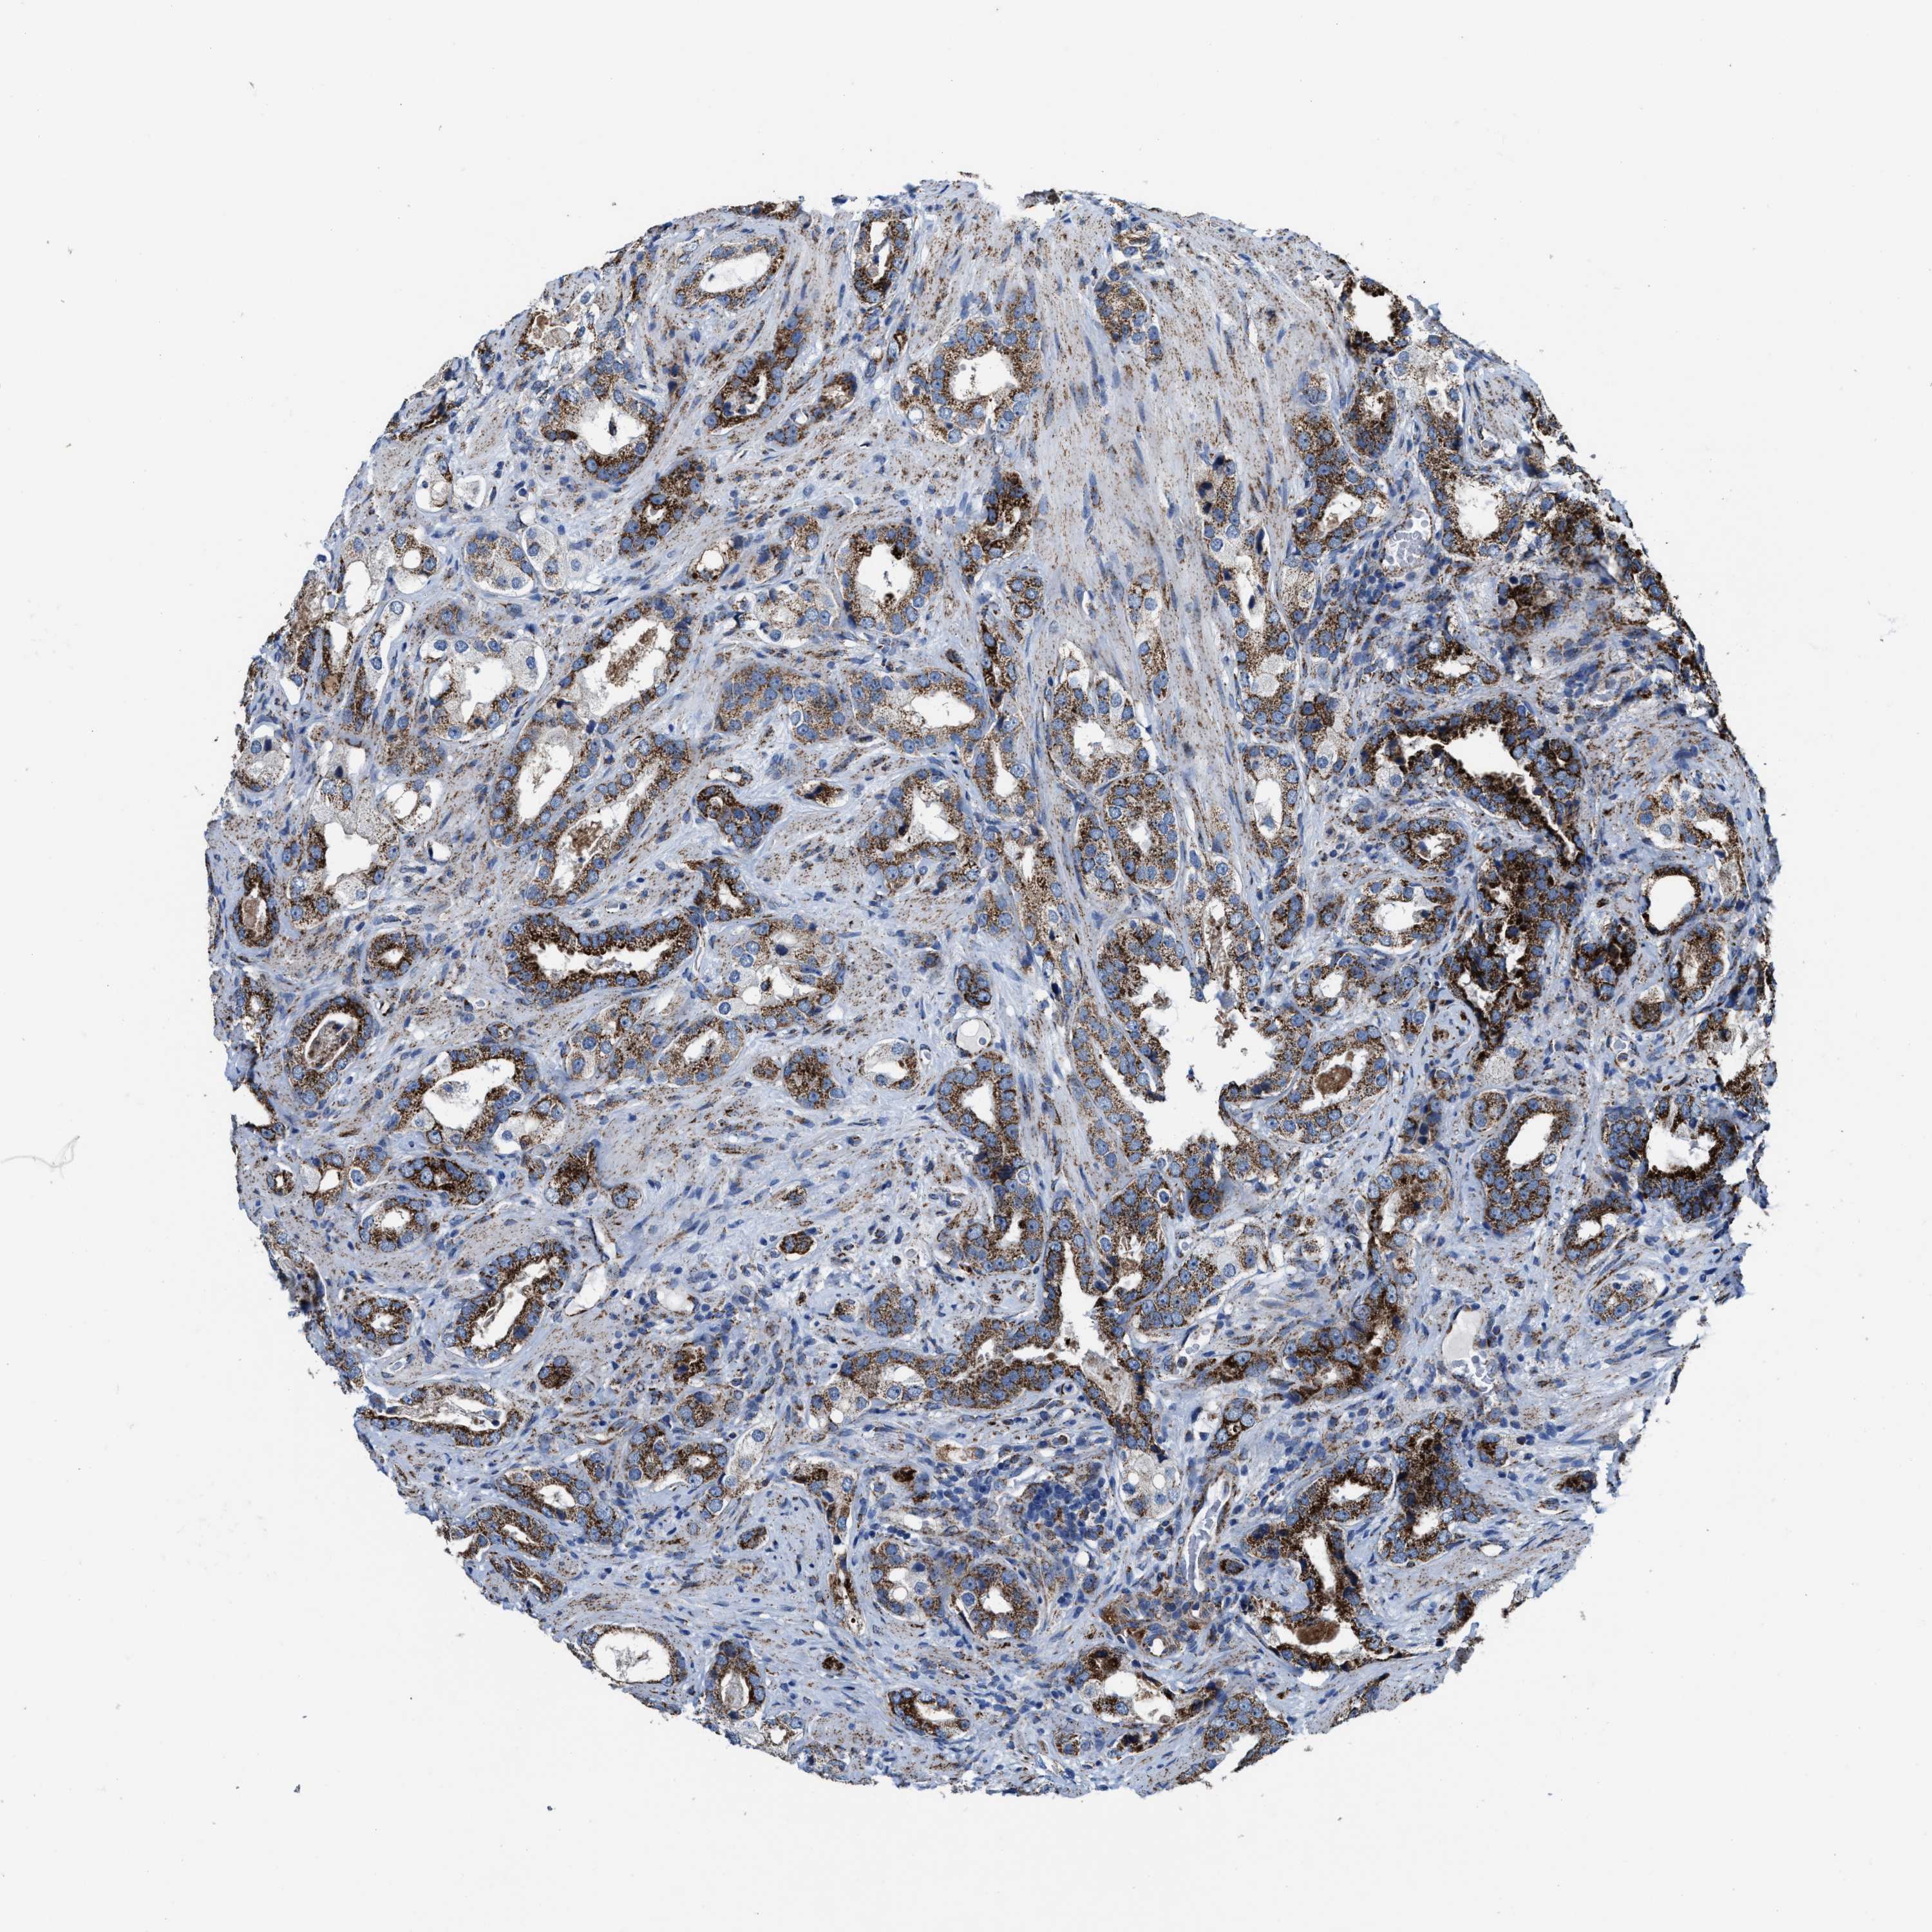

PROSTATE CANCER - Protein expressioni

A mouse-over function shows sample information and annotation data. Click on an image to view it in a full screen mode. Samples can be filtered based on level of antibody staining by selecting one or several of the following categories: high, medium, low and not detected. The assay and annotation is described here.

Note that samples used for immunohistochemistry by the Human Protein Atlas do not correspond to samples in the TCGA dataset.

Antibody stainingi

Antibody staining in the annotated cell types in the current human tissue is reported as not detected, low, medium, or high, based on conventional immunohistochemistry profiling in selected tissues. This score is based on the combination of the staining intensity and fraction of stained cells.

Each image is clickable and will lead to virtual microscopy that enables deeper exploration of all samples and also displays staining intensity scores, fraction scores and subcellular localization as well as patient and tissue information for each sample.

Antibody HPA021037

Antibody HPA077080

Staining

High

Medium

Low

Not detected

Intensity

Strong

Moderate

Weak

Negative

Quantity

>75%

75%-25%

<25%

None

Location

Nuclear

Cytoplasmic/membranous

Cytoplasmic/membranous,nuclear

Adenocarcinoma, High grade

Adenocarcinoma, Low grade

Adenocarcinoma, Medium grade

Adenocarcinoma, NOS